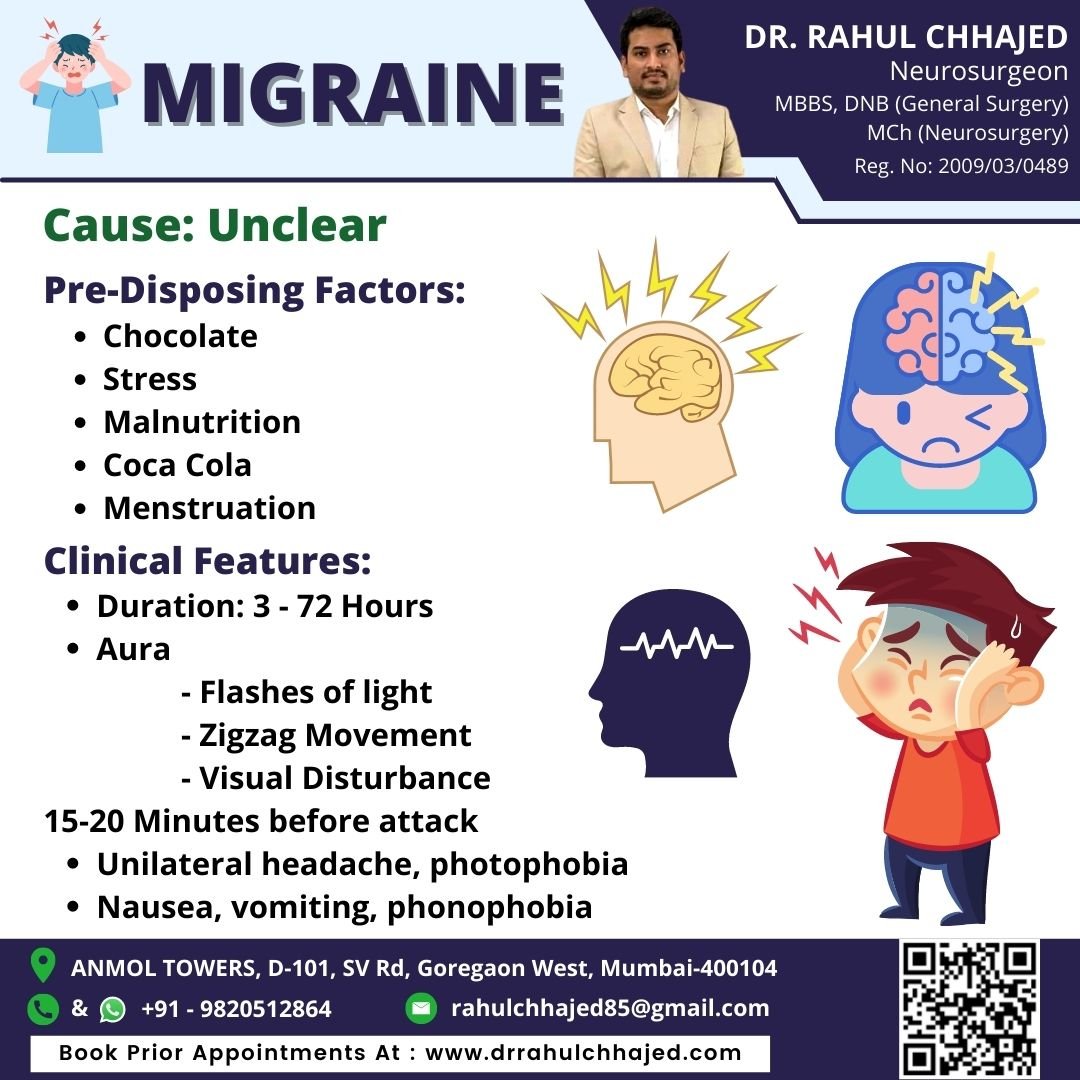

Headache

At our clinic, we understand that headaches can greatly impact your daily life and productivity. Whether you suffer from migraines, tension headaches, or another type of headache disorder, we are dedicated to providing compassionate care and helping you find relief.